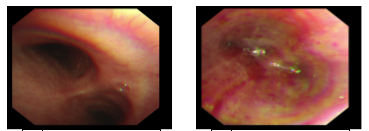

为鉴别癌症的可能,葛海波主任当机立断行电子支气管镜检查+肺泡灌洗术,镜下:支气管管腔未见新生物,仅及大量白色透明状粘痰。

吴先生临床症状虽改善,但结合影像学检查,葛海波主任坚持认为不排除肺部恶性疾病的可能,与吴先生充分沟通后,立即完善电子支气管镜检查,镜下:右肺中叶内侧段及外侧段支气管闭塞,见新生物,行活检,并行肺泡灌洗术。